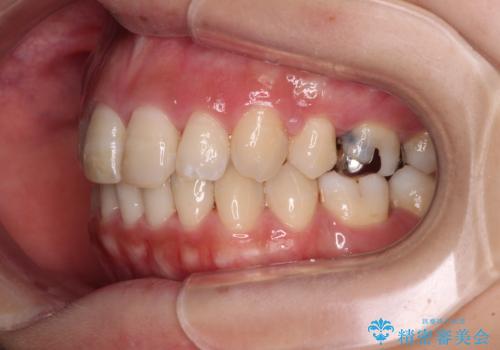

突出した口元が気になる ハーフリンガル装置による抜歯矯正

- 口元の突出感を気にして来院された患者様です。

通常では上下左右の第一小臼歯4本を抜歯しますが、下顎が左側にシフトしていたため、下顎左側のみ第二小臼歯を抜歯し、正中を合わせながら口元を下げる治療計画としました。